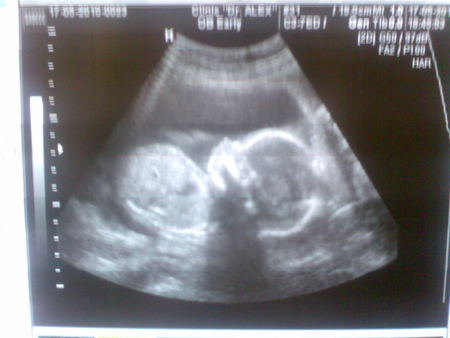

Викки 15 лет А вот мы в животике в 20 недель! Посмотрите еще 20 записей на эту тему Отменить Ответить WL класс! а у нас есть видео с узи на 28 й неделе 17.11.2010 Ответить Викки У нас к сожалению видео нету! 17.11.2010 Ответить Я вся извелась-этот кашель!!!!!!!!!!!!!!!!!!!!!!!!!!!!!!!!!!!!! Можно ли что-то приготовить из детской смеси? Чаты Беременных Выберите чат: Январята-2026 Февралята-2026 Мартята-2026 Апрелята-2026 Майчата-2026 Июнята-2026 Июлята-2026 Августята-2026